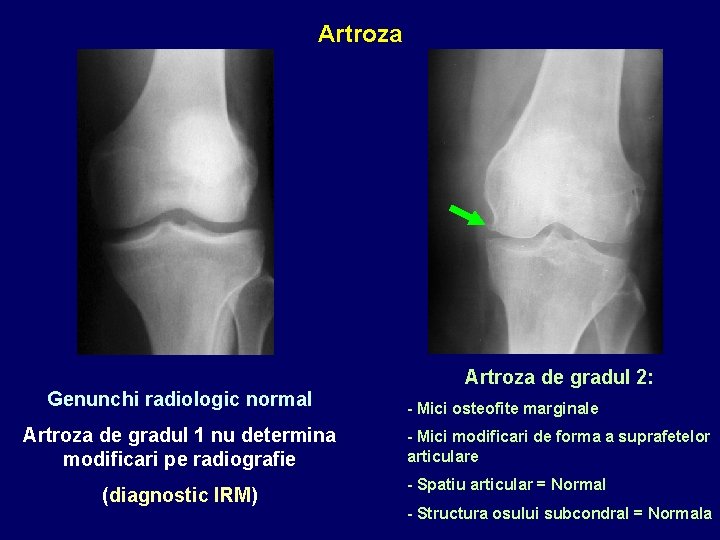

Artroza de gradul 2: Genunchi radiologic normal Artroza de gradul 1 nu determina modificari pe radiografie (diagnostic IRM) - Mici osteofite marginale - Mici modificari de forma a suprafetelor articulare - Spatiu articular = Normal - Structura osului subcondral = Normala

Artroza de gradul 3: Artroza de gradul 4: - Osteofite marginale mari = Ankiloza - Modificari de forma a suprafetelor articulare - Disparitia spatiului articular - Spatiu articular = diminuat - Osteoscleroza - Os subcondral cu plaje de demineralizare/liza (geode subcondrale) - Sindesmofite care creeaza punti